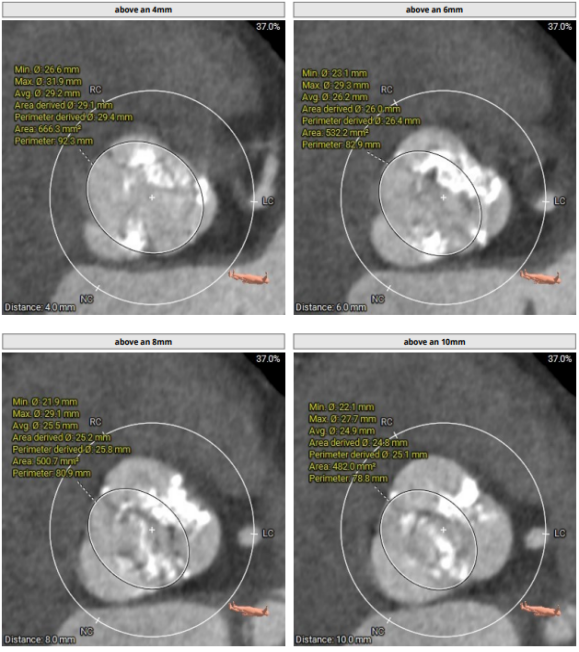

主动脉根部:功能型二叶瓣,瓣叶增厚,重度钙化,左右可见钙化融合。左冠开口高度约14mm,右冠开口高度约15.4mm。法式窦结构大,STJ高度约20.2mm、直径约30.6mm。升主动脉未见明显扩张,心脏角度约54°。左室大小尚可,心肌增厚。CT显示患者结构偏大,瓣环及流出道成敞口状。瓣上各辅助锚定区域处于临界值,给手术操作带来挑战。 请注意,我没有改变原文的意思。

功能型二叶瓣,瓣叶增厚,重度钙化,左右可见钙化融合,左冠开口高度约1 4mm,右冠开口高度约1 5.4mm,法式窦结构大,STJ高度约20.2mm、直径约30.6mm,升主动脉未见明显扩张,心脏角度约54°,左室大小尚可,心肌增厚。CT显示患者结构偏大,瓣环及流出道成敞口状,瓣上各辅助锚定区域处于临界值,给手术操作带来挑战

1患者患有功能型二叶瓣,瓣叶增厚,左右瓣叶间有钙化融合。左冠开口高度为14mm,右冠开口高度为15.4mm。法式窦结构较大,平均径为35.1mm。STJ高度为20.2m,直径为30.6mm。经过综合评估,在瓣膜释放过程中,位置难以控制,存在下滑移位甚至瓣中瓣的风险。